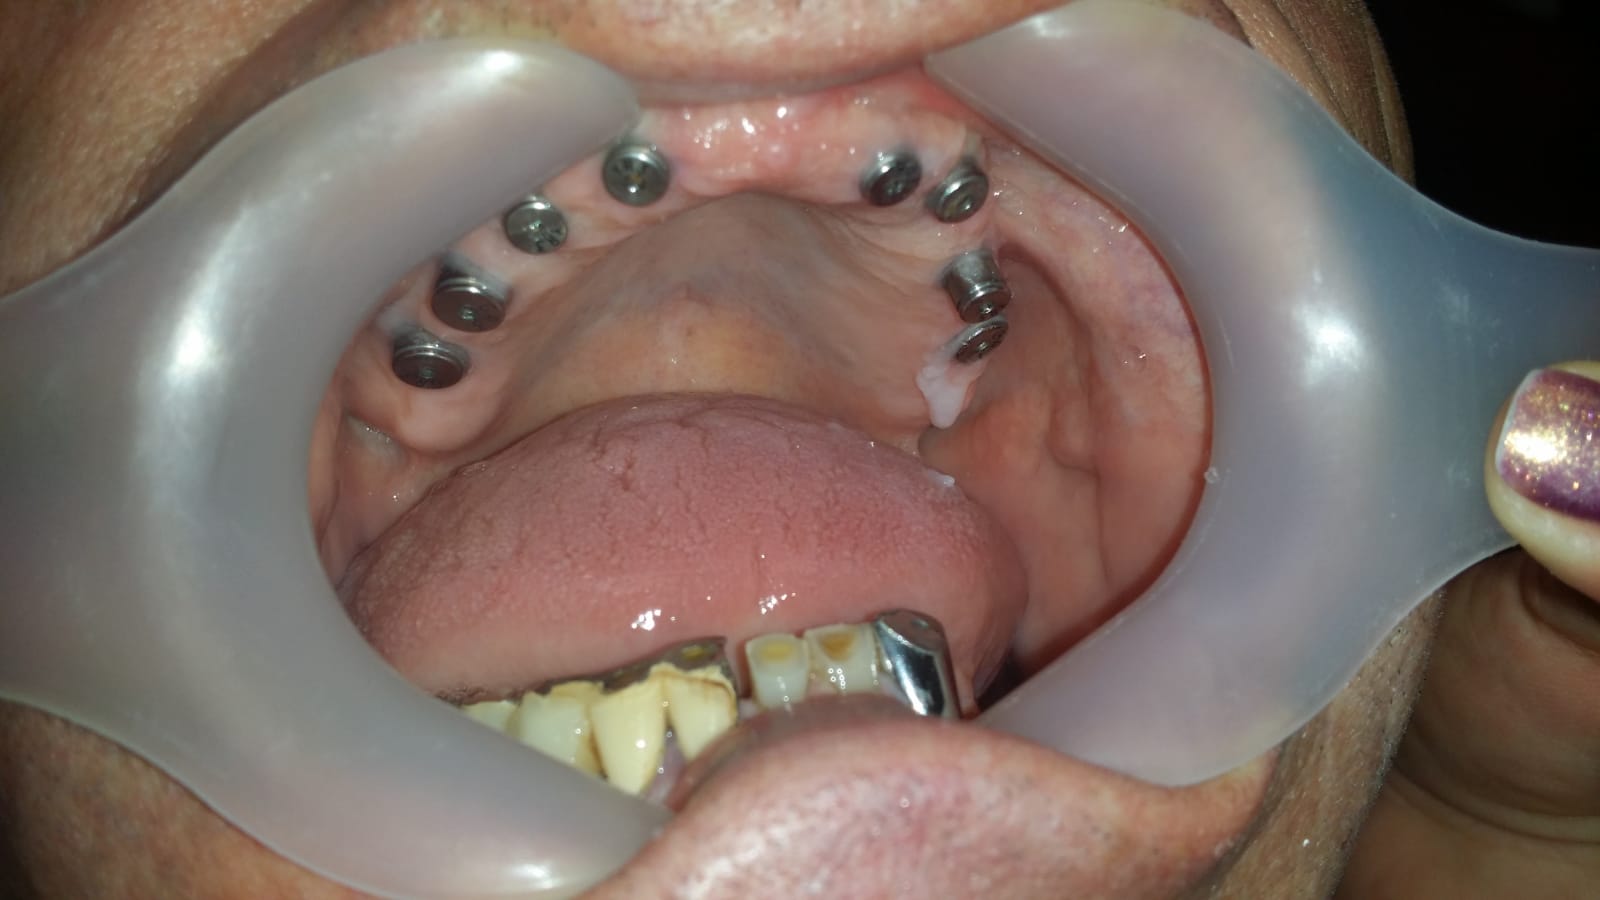

Punte realizată pe 4 implanturi dentare la mandibula și 6 implanturi la maxilar All in One

Reabilitare pe implanturi dentare

Fast and fixed definitiv